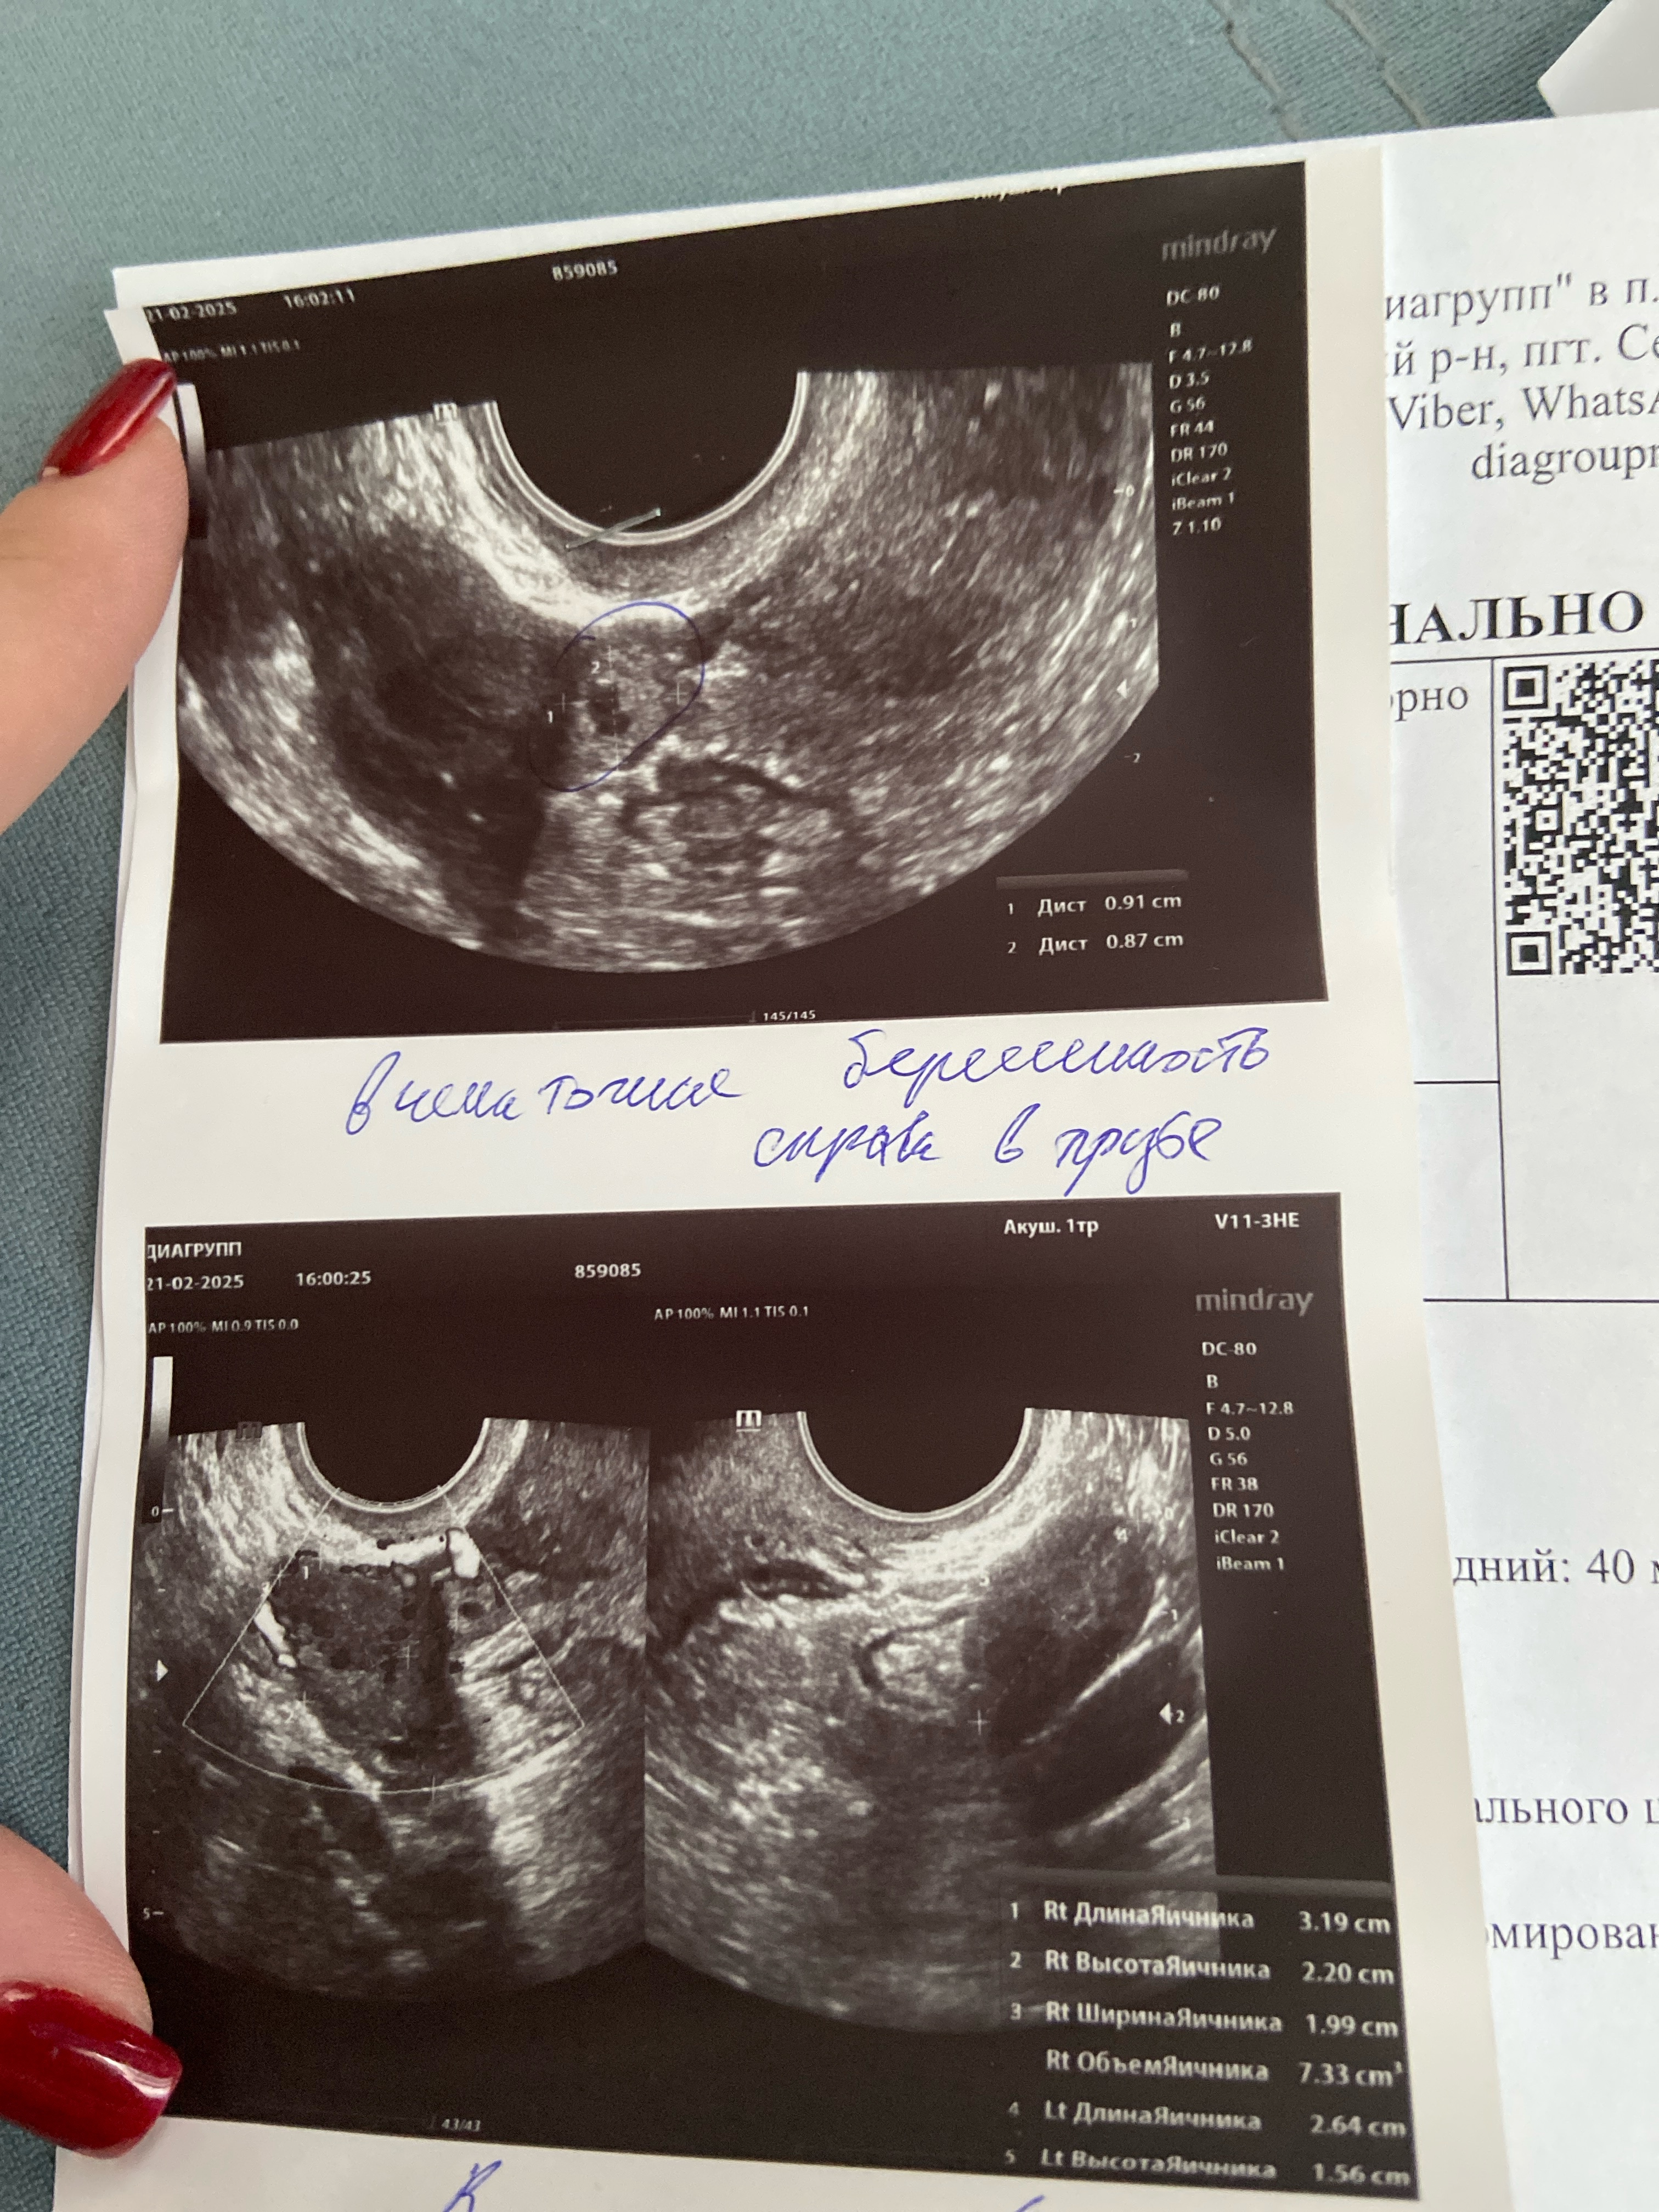

Юлия 10 месяцев Похоже на плодное яйцо ? Или возможно это что-то другое… Посмотрите еще 20 записей на эту тему Отменить Ответить Наталья Добрый вечер, подскажите, чем по итогу закончилась ваша беременность? 30.03.2025 Ответить Подозрение на внематочную Чаты Беременных Выберите чат: Январята-2026 Февралята-2026 Мартята-2026 Апрелята-2026 Майчата-2026 Июнята-2026 Июлята-2026 Августята-2026